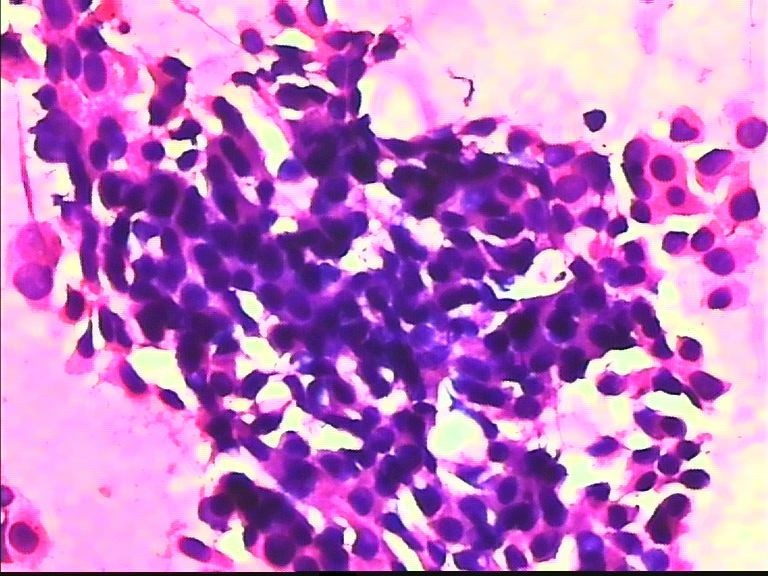

38岁 乳腺肿瘤 女

• 38岁 乳腺肿瘤 女图4

图4

考虑癌:图18细胞核形式不规则,染色质粗块状,可见核仁.

乳腺癌

乳腺癌。

浸润导管癌

好像重复了。浸润性导管 癌。

从所给图看恶性是没什么问题!染色有点过,染色质结构欠清晰;关于细胞学判断浸润的问题我想应综合来判断,如单个细胞的异形性,细胞整体弥散情况,细胞微粒结构以及间质成分等等,个人的认识也起到一定因素,细针穿刺中最常规用的还是--导管癌。